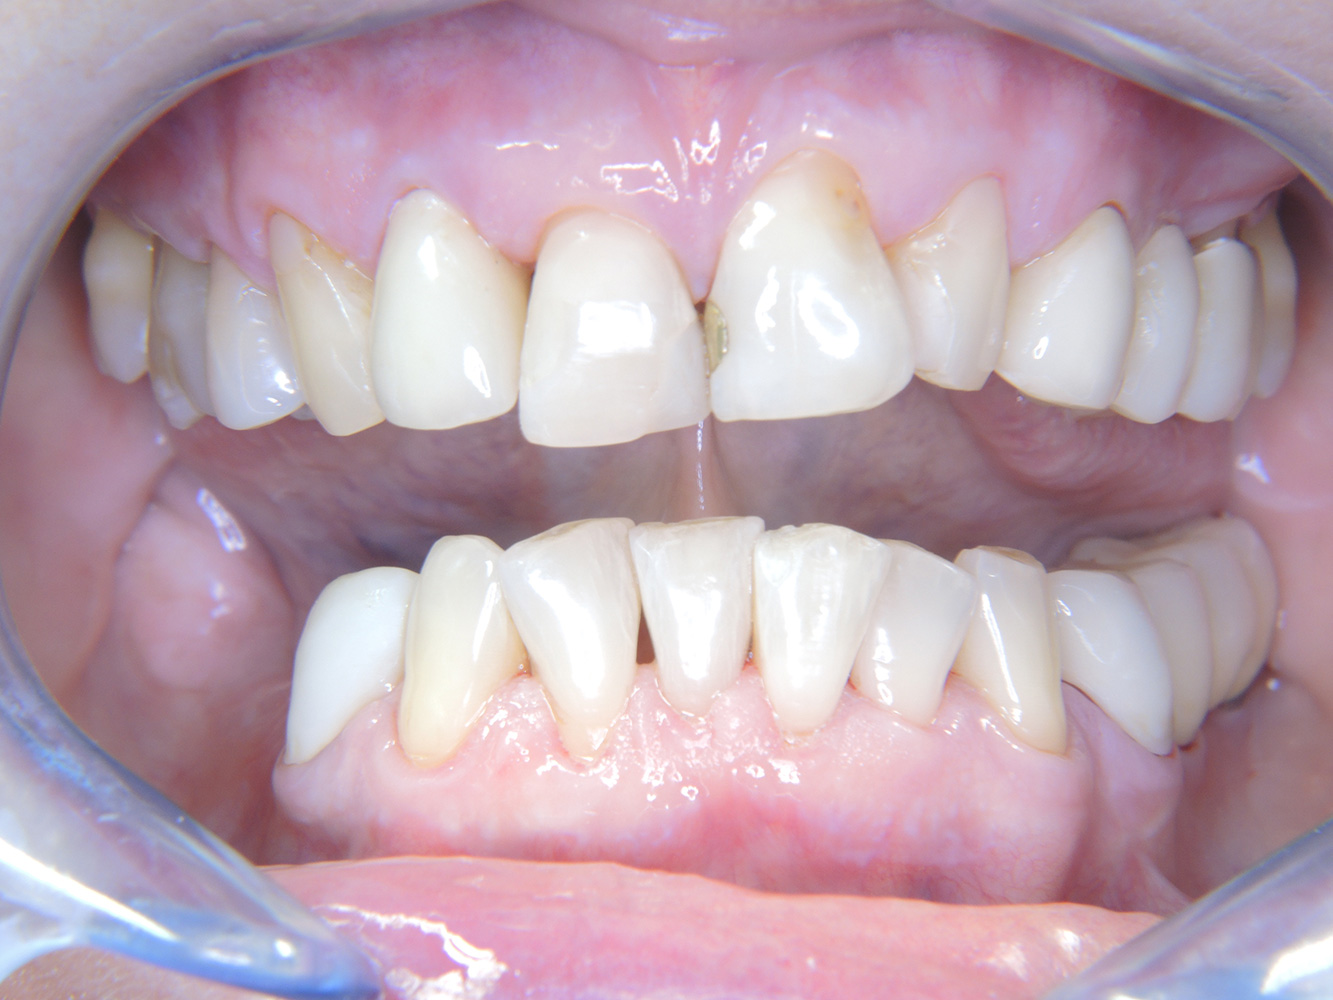

The 68-year-old patient has no general health conditions and is not taking any medication that may be relevant to her oral health, and her lifestyle does not pose any particular risk. The patient has two dental implants (3rd quadrant, for five years) and a previous case of periodontal disease (stage IV, grade B periodontitis) with tooth loss. Currently the periodontal conditions are stable. However, periodontitis significantly increases the biological complications of implantations and there is a risk of implant loss (21). Four recommendations can be determined for the prophylaxis session.

As the patient does not have any particular risk factors with specific dental implications, the requirements determined from her current state of oral health are crucial. Here, it is recommended that a thorough assessment of periodontal condition be carried out once a year. This will ensure that any potential progression of the previous periodontal disease or development of peri-implantitis can be responded to in good time.

Despite the stable conditions, it is also crucial for the instructive/motivational discussion to be conducted with this patient. Particular attention should be paid to teaching the patient how to care for the implants correctly. Here in particular, good at-home maintenance can have a significant impact on the long-term stability of oral and implant health.

In terms of instruments, specific procedures are required for use with implants. In order to preserve the surface of the implant while cleaning it effectively, it is essential to choose suitable powders and instruments such as the targeted use of air polishing devices with special periodontal tips. Which powder is most suitable can be determined according to the needs and risk. For example, in addition to the appropriate degree of abrasion, dietary requirements (including sugar-free, low-salt) may also be taken into account.

Because the patient has implants and a history of periodontal disease, she is at risk of developing peri-implantitis. It is therefore recommended that she attend a recall session every three to four months.